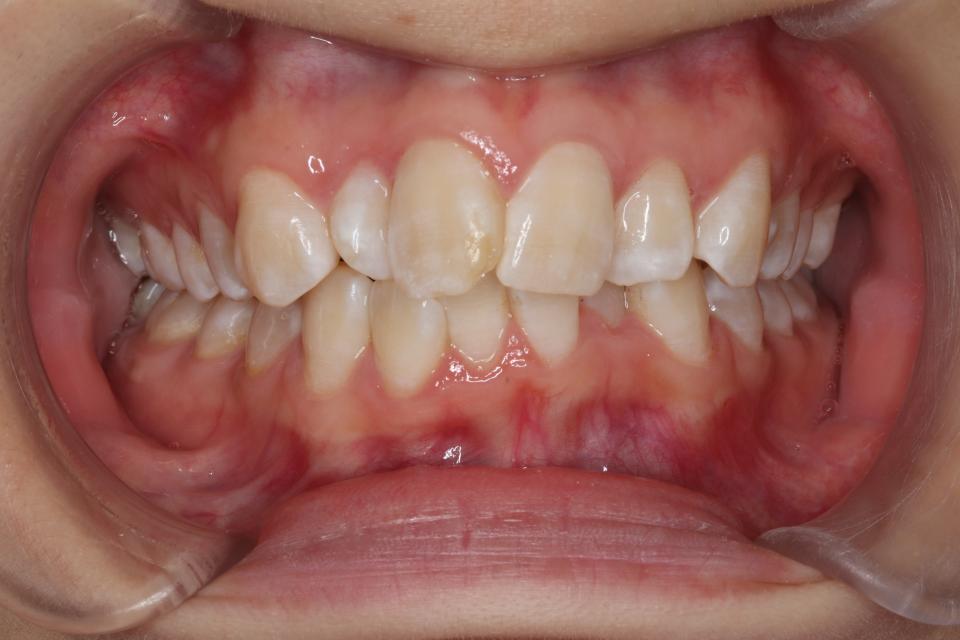

がたがた(叢生)のワイヤー矯正治療例(抜歯あり)

矯正治療前

20代女性の患者さんです。

下の前歯のがたつきを気にして来院されました。